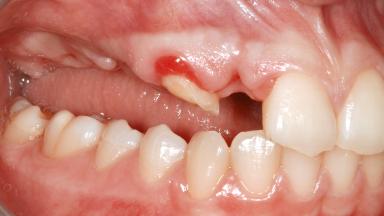

Ridge Preservation and Implant Placement for a Fixed Dental Prosthesis After a Car Accident

It is well known to clinicians that any removal of teeth will, over time, cause the dimensions of the alveolar ridge to be reduced by resorption of the bundle bone and by changes related to external modeling. This development is particularly evident in the crestal region with its thin buccal bone that consists of bundle bone almost entirely. The facial bone will rapidly resorb as blood supply from the periodontal ligament gets disrupted (Araújo and Lindhe 2005). There is no reason why traumatic tooth loss should not have the same consequences. It takes more than achieving implant osseointegration for a treatment outcome to be considered successful. No deficiency of bone or soft tissue is acceptable when an ideal esthetic outcome is the goal. Several articles (Sanz and coworkers 2011; Vignoletti and coworkers 2011) have reported on techniques of improving the alveolar ridge for implant treatment, notably focusing on protecting tissues from resorption.

Infection at Implant Site None Chronic Acute

Soft Tissue Anatomy Intact Defective

Bone Volume Horizontally and vertically sufficient Horizontally deficient Deficient vertically or deficient vertically AND horizontally